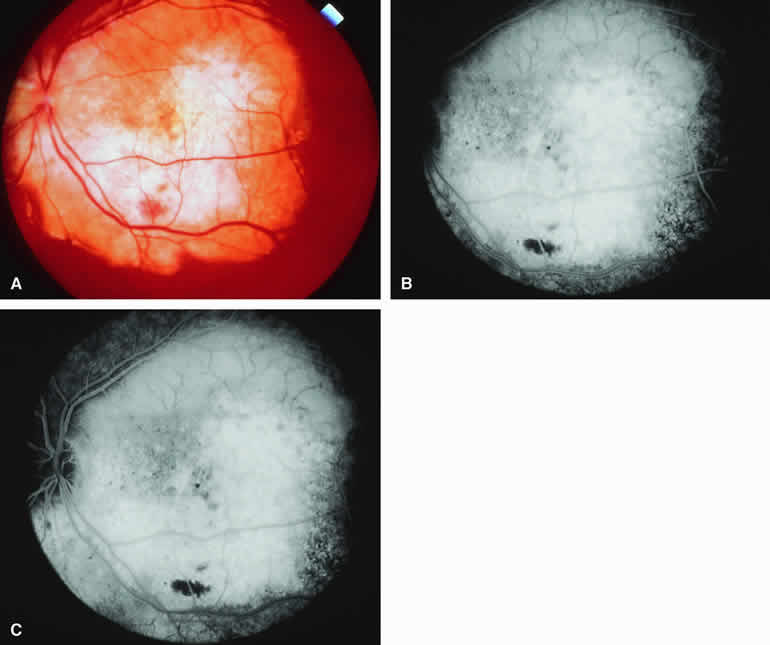

selected choroidal tumors are described and illustrated. CHOROIDAL NEVUS The choroidal nevus is a benign uveal melanocytic tumor of limited growth potential. The typical lesion (Figs. 1, 2, 3, and 4) appears as an ill-defined, gray-brown choroidal mass that is usually less than 5 mm in maximal basal diameter and less than 1 mm in thickness. The basal margins of typical lesions often blend into the normal surrounding choroid in a feathered or striate pattern. Drusen and retinal pigment epithelial (RPE) pigment clumps commonly develop on the surface of these tumors. Fluorescein and ICG angiographic features of choroidal nevi have been described by numerous authors.1, 2, 3, 4, 5, 6, 7, 9, 10, 11, 12 Neither fluorescein nor ICG angiography appears to be particularly helpful for evaluation of a typical choroidal nevus. Ophthalmoscopy is usually sufficient to allow one to decide with reasonable certainty whether a small melanotic choroidal tumor is a typical choroidal nevus or an equivocal lesion that may be either a large nevus or small choroidal melanoma. No well-designed clinical study has ever demonstrated significant independent differential diagnostic value of fluorescence angiography for clarifying this differential diagnosis.8 Typical Melanotic Choroidal Nevus Fluorescein angiography of a typical choroidal nevus with bland surface features (see Fig. 1) shows the entire lesion to be hypofluorescent relative to the adjacent uninvolved choroid throughout the study. No large-caliber choroidal blood vessels are usually identifiable within the lesion. The retinal vasculature overlying the lesion appears well defined and normal on fluorescein angiography. ICG angiography of a typical melanotic choroidal nevus (see Fig. 2) shows better definition of the basal area of the lesion than does fluorescein angiography. The entire lesion appears completely and uniformly dark throughout the ICG angiogram. Only the larger retinal blood vessels overlying the nevus are usually demonstrated on ICG angiography. Amelanotic Choroidal Nevus Approximately 10% to 15% of choroidal nevi are largely or completely amelanotic clinically. Fluorescein and ICG angiography of an amelanotic choroidal nevus (see Fig. 3) tend to show less prominent hypofluorescence of the lesion than they do with darkly melanotic nevi. Because of the lack of intracellular melanin pigment within the nevus cells, some large-caliber choroidal blood vessels running through the nevus may be visible in the region of the mass (see Fig. 3B and C). These choroidal blood vessels are better defined by ICG angiography than by fluorescein angiography. Amelanotic choroidal nevi often appear mildly hyperfluorescent in late-phase frames (see Fig. 3D). Choroidal Nevus with Drusen and Clumps of RPE Hyperplasia If a choroidal nevus has drusen and RPE alterations on its surface (see Fig. 4A), fluorescein angiography (Fig. 4B, C, and D) tends to show patchy or stippled window defect hyperfluorescence corresponding to foci of RPE depigmentation, fluorescence blockage by clumps of RPE hyperplasia on the surface of the lesion, and late staining of at least some of the drusen. These features are not usually as evident on ICG angiography as they are on fluorescein angiography. Choroidal Nevus Versus Melanoma Small melanocytic choroidal tumors larger than 5 mm in diameter and thicker than 1 mm but without clearly invasive clinical features (e.g., nodular eruption through Bruch's membrane, retinal invasion) may be either benign nevi or small choroidal melanomas. Several features of these lesions have been identified as prognostic of the likelihood of subsequent lesion enlargement,13 a surrogate indicator of the malignant potential of the tumor. Features suggestive of low growth potential and probable benign histology include thickness less than or equal to 1.5 mm, uniform gray-brown coloration of the lesion, and drusen and RPE clumping on the surface of the lesion. In contrast, features suggestive of higher growth potential and probable malignant histology include thickness greater than 1.5 mm, nonuniform coloration of the lesion, prominent clumps of lipofuscin pigment on the surface of the lesion, and serous subretinal fluid overlying and surrounding the lesion. None of these features is a reliable indicator of the underlying histologic nature of the tumor; however, the greater the number of unfavorable features, the greater the likelihood of lesion enlargement if it is followed without treatment after initial detection. Choroidal Nevus Versus Melanoma with Bland Surface Features Several authors have evaluated fluorescein and ICG angiography as differential diagnostic tools for differentiating between large benign choroidal nevi and small malignant choroidal melanomas.9, 10 An example of such a lesion evaluated by fluorescein angiography is presented as Figure 5. Some common assertions based on these studies include the following. If the lesion is a nevus, fluorescein angiography is likely to show hypofluorescence of the lesion throughout the study, absence of large-caliber intralesional blood vessels, and lack of late smudgy hyperfluorescence resulting from leakage from these vessels. In contrast, if the lesion is a melanoma, fluorescein angiography is likely to show at least some intralesional tumor blood vessels, some patchy or smudgy fluorescein leakage from those blood vessels, and at least patchy or smudgy late fluorescence of the tumor. ICG angiography is more likely to reveal intralesional blood vessels within bland appearing small melanocytic choroidal lesions (especially darkly melanotic lesions) than is fluorescein angiography, and lesions with prominent intralesional blood vessels are generally regarded as more likely to be melanomas. Unfortunately, there have been no confirmatory angiographic-histopathologic correlation studies of small melanocytic choroidal tumors in the nevus versus melanoma category to confirm or refute these assertions. At best, this author regards the fluorescence angiographic features of bland appearing small melanocytic choroidal tumors as suggestive but not confirmatory of the pathologic nature of the tumor. Choroidal Nevus Versus Melanoma with Prominent Lipofuscin Pigment Clumps If one obtains a fluorescein angiogram on a small melanotic choroidal lesion (nevus versus melanoma) that has prominent clumps of lipofuscin pigment on its surface (Fig. 6), the pigment clumps appear intensely hypofluorescent throughout the study. This appearance is attributable to the complete blocking of choroidal fluorescence by the lipofuscin. ICG angiography does not show lipofuscin pigment clumps on the surface of the tumor as well as fluorescein angiography does. Choroidal Nevus Versus Melanoma with Overlying Serous Subretinal Fluid A blister of serous subretinal fluid sometimes develops over and around a presumed choroidal nevus (Fig. 7A), especially if the lesion is located in the macula.11 If one performs a fluorescein angiogram on a small melanocytic choroidal lesion (nevus versus melanoma) that has shallow overlying serous subretinal fluid (see Fig. 7B, C, and D), one or more hyperfluorescent leak sites may show up slowly at the RPE level as the study progresses. In some cases, fluorescein will clearly leak from those foci into the overlying serous subretinal fluid. ICG angiography does not show hyperfluorescent leak sites at the RPE level as well as fluorescein angiography does. Choroidal Nevus Versus Melanoma with Choroidal Neovascular Membrane A choroidal neovascular membrane occasionally develops from the surface of a small melanocytic choroidal tumor (nevus versus melanoma).12 This vascular structure can usually be anticipated because of the presence of ophthalmoscopically evident hemorrhagic or exudative subretinal fluid overlying a portion of the tumor (Fig. 8A). Fluorescein angiography in such cases (see Fig. 8B to D) generally reveals the neovascular membrane as a relatively well-defined vascular network that fluoresces brightly in the early frames of the study and leaks progressively by the late frames. If the subretinal fluid is grossly hemorrhagic, ICG angiographymay show the choroidal neovascular network better than does fluorescein angiography.